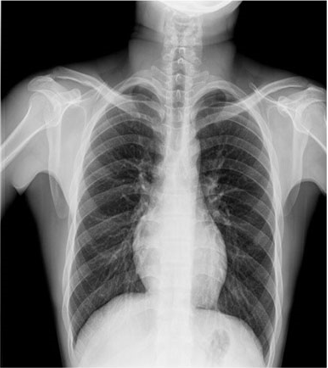

卓越的影像鏈配置是獲得優質影像的有力保障:普利德車載DR采用高頻高壓發生器、大熱容量球管確保穩定、精確的射線輸出;17X17英寸大尺寸無線平板探測器,更大的視野范圍,更高的靜態空間分辨率,確保呈現清晰影像。

普利德車載DR可進行胸部等部位的X射線數字攝影檢查,滿足大規模體檢及傳染疾病控制需求,尤其在重大疫情預防等應急檢查工作中具有突出優勢,為各級醫療機構快速應對突發性公共衛生事件提供強大助力,實力護航健康之路。